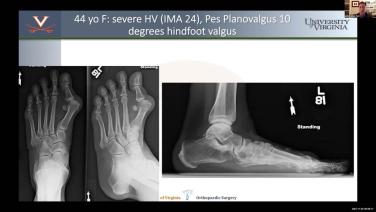

Master Class on Foot Deformities with Matt Hope, MD - Part 2

Master Class on Foot Deformities with Joseph Park, MD - Part 5